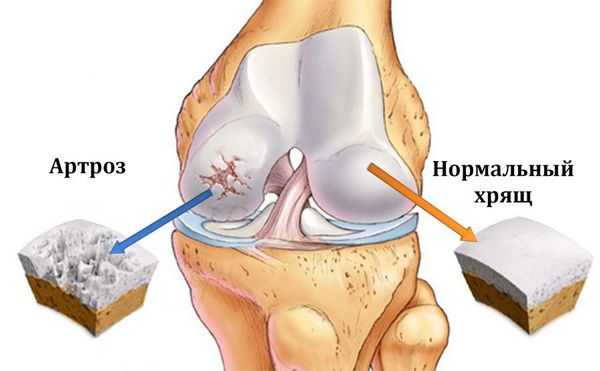

• Невоспалительная артропатия с прогрессирующим разрушением хряща, приводящая к гипертрофическим изменениям кости

• Невоспалительное заболевание сустава, характеризующееся прогрессирующим разрушением хряща:

о Приводит к гипертрофическим костным изменениям